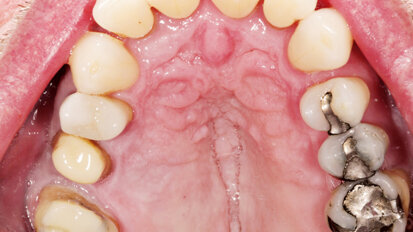

Rehabilitace Straumann

Po. 1. února 2021